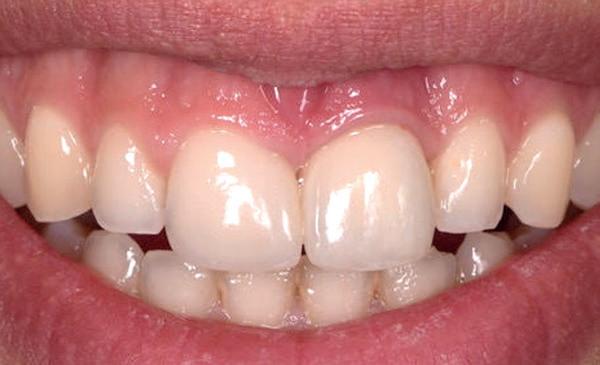

patiënt kon 2 maanden functioneren met de tijdelijke brug, waarna een kort consult werd gepland om te bespreken of hij tevreden was met de esthetiek en functie. Voor de patiënt hoefde niks veranderd te worden (afbeelding 11-14).

14. Portretfoto met tijdelijke brug

De technicus leverde op basis van de tijdelijke brug, de vast brug op implantaten af. Deze is van volledig zirkoonoxide met een titanium frame aan de binnenzijde voor de stevigheid (afbeelding 16-18). Een volledige brug van alléén zirkoonoxide is namelijk fractuur gevoelig. Na verwijderen van de tijdelijke brug kon de mondhygiëne van de patiënt gecontroleerd worden bij de implantaten. Patiënt hield het netjes schoon met een elektrische tandenborstel en een waterpik. Het is van belang dat de brug zonder spanning op zijn plek geduwd kan worden en deze niet kan kantelen op de abutments. Na het plaatsen van de brug werden de schroefjes getorqued op 15 Ncm, waarna de esthetiek, occlusie en articulatie gecontroleerd konden worden.

Daarna werden de schroefgaten gevuld met Blue M gel, teflon tape en composiet (afbeelding 19 en 20). Patiënt was zich zeer tevreden met het functionele en esthetische eindresultaat (afbeelding 19 en 20). Er was ook een nette hoektand en frontgeleiding. Voor de fonetiek werd een filmpje opgenomen, de F en de S werden netjes uitgesproken (afbeelding 21). De patiënt vervolgt zijn parodontale nazorg bij de mond-

hygiënist waarbij ook de mondhygiëne bij de brug wordt gecontroleerd. Op de OPT na 2 jaar (afbeelding 22) is het botniveau rondom de implantaten stabiel en is patiënt tevreden met zijn vaste brug.

21. Portretfoto na 2 jaar